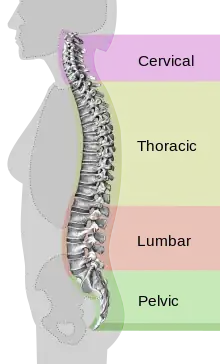

| Different regions (curvatures) of the vertebral column | |

Back pain (Latin: dorsalgia) is pain felt in the back. It may be classified as neck pain (cervical), middle back pain (thoracic), lower back pain (lumbar) or coccydynia (tailbone or sacral pain) based on the segment affected.[1] The lumbar area is the most common area affected.[2] An episode of back pain may be acute, subacute or chronic depending on the duration. The pain may be characterized as a dull ache, shooting or piercing pain or a burning sensation. Discomfort can radiate to the arms and hands as well as the legs or feet,[3] and may include numbness[1] or weakness in the legs and arms.